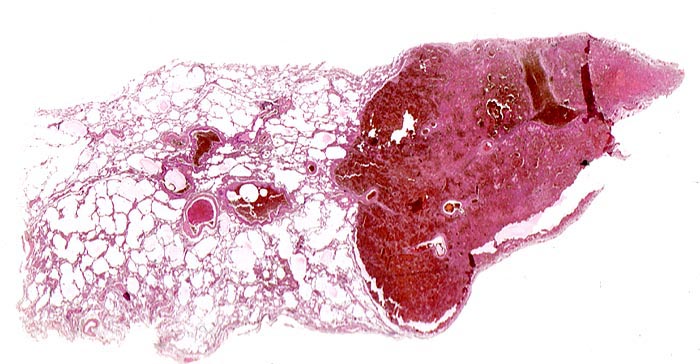

Makroskopisch bilden sie ein Dreieck mit der Basis an der Pleuraoberfläche, sind leicht erhaben, dunkelrot gefärbt und induriert. Innerhalb von 48 Stunden beginnen die Erythrozyten zu zerfallen und der Infarkt wird von aussen her narbig organisiert.

• Scharf begrenzte dreiecksförmige hämorrhagische Nekrose des Lungenparenchyms.

• Pulmonalarterienast mit nicht wandhaftendem Thrombembolus am Rand des Infarktes.